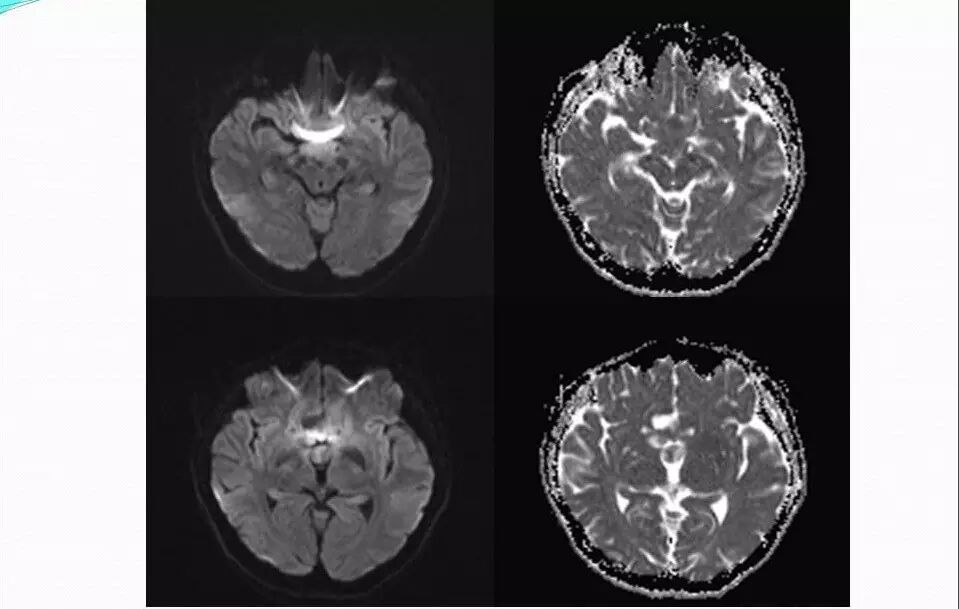

2.MR检查显示肿瘤位于鞍区,分叶状生长,呈稍长T2、稍长T1异常信号影,边界清楚,内部信号不均匀,其内可见“微囊”状异常信号影,视交叉受压上抬,DWI呈等或略高信号影,注药后呈不均匀明显强化;

4.重点观察冠状位:病变源于垂体偏左侧,与垂体界限不清楚,肿瘤偏右侧可见垂体与肿瘤之间裂隙,造成矢状位平扫及强化后误认为正常垂体存在,从而首先除外了垂体瘤,导致误诊;